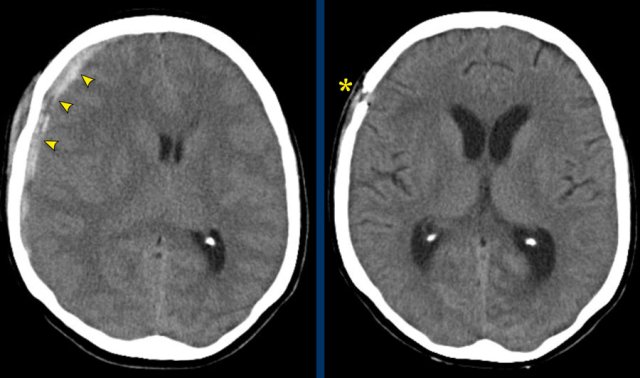

The images show a subdural hematoma.

Notice that the hematoma has both hyperdense and isodense  areas.

This can be seen in hyperacute bleeding, but can also be seen in rebleeding.

There is displacement of midline structures with obstruction of CSF flow resulting in dilatation of the temporal horn of the right lateral ventricle (arrow).

An acute subdural hematoma is hyperdens (clotted blood), a subacute hematoma is isodens and a chronic subdural hematoma appears hypodens to brain parenchyma (isodens to CSF).

Subacute isodense subdural hematoma(3-21 days). Subacute isodense subdural hematoma(3-21 days).

Isodense subdural hematoma

As a subdural hematoma ages, the density of the hematoma will decrease and may be the same as the density of the brain, which make it difficult to detect the hematoma.

Here a case of an isodense subdural hematoma which is very hard to detect (arrows).

Notice that on a higher level there is a bilateral subdural hematoma.